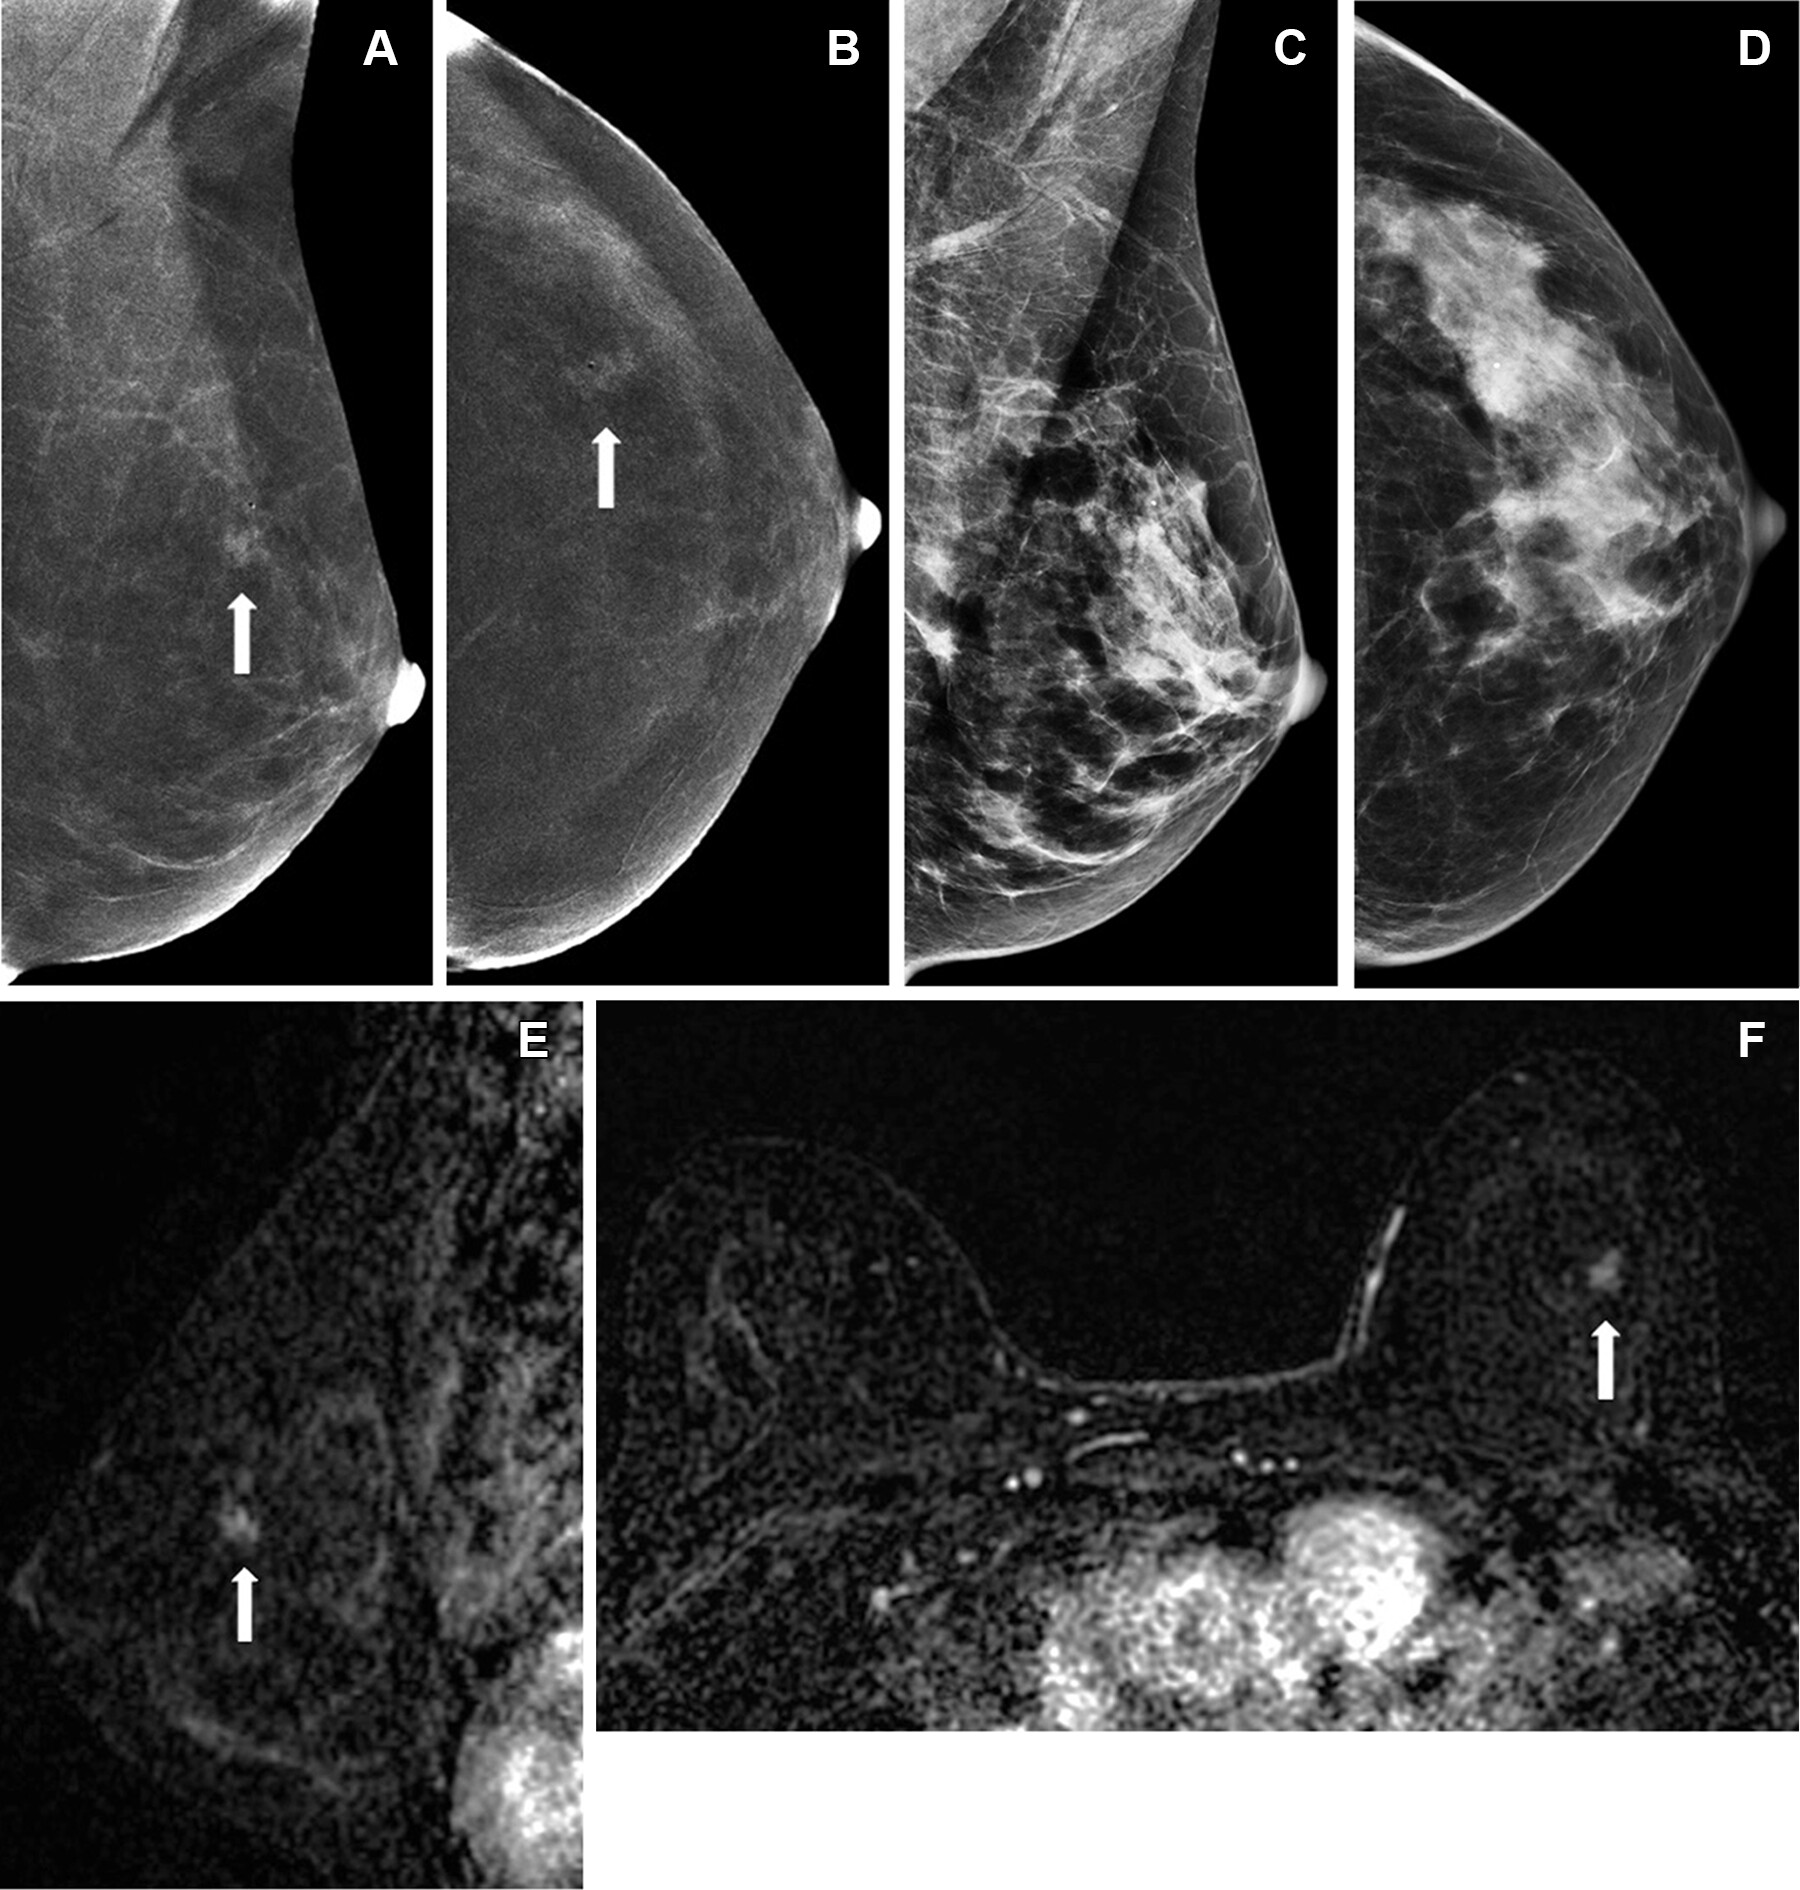

Mammography is the traditional modality for both screening for breast cancer and follow-up of suspicious results, but it has its limits, notably less ability to identify cancer in dense breast tissue. Ultrasound offers another screening tool and can overcome some of mammography's limitations. But contrast-enhanced imaging shows promise for breast cancer diagnosis in that it provides functional information regarding tumor vascularity that "strongly boosts the cancer detection rate in screening and also improve staging," the team explained.

- When compared with standard mammography for diagnosing breast cancer, CEM has shown improved sensitivity (90.5% vs. 52.4%) but also reduced specificity (76.1% vs. 90.5%). Previous research has estimated breast MRI's sensitivity to be up to 100% and its specificity up to 98%.

- MR imaging excels at visualizing areas not well seen on mammography, such as far posterior locations or the axilla. But it's also more expensive and not always covered by insurance.

- One of CEM's main limitations compared to breast MRI is its lower ability to visualize the axillary regions of the breast.